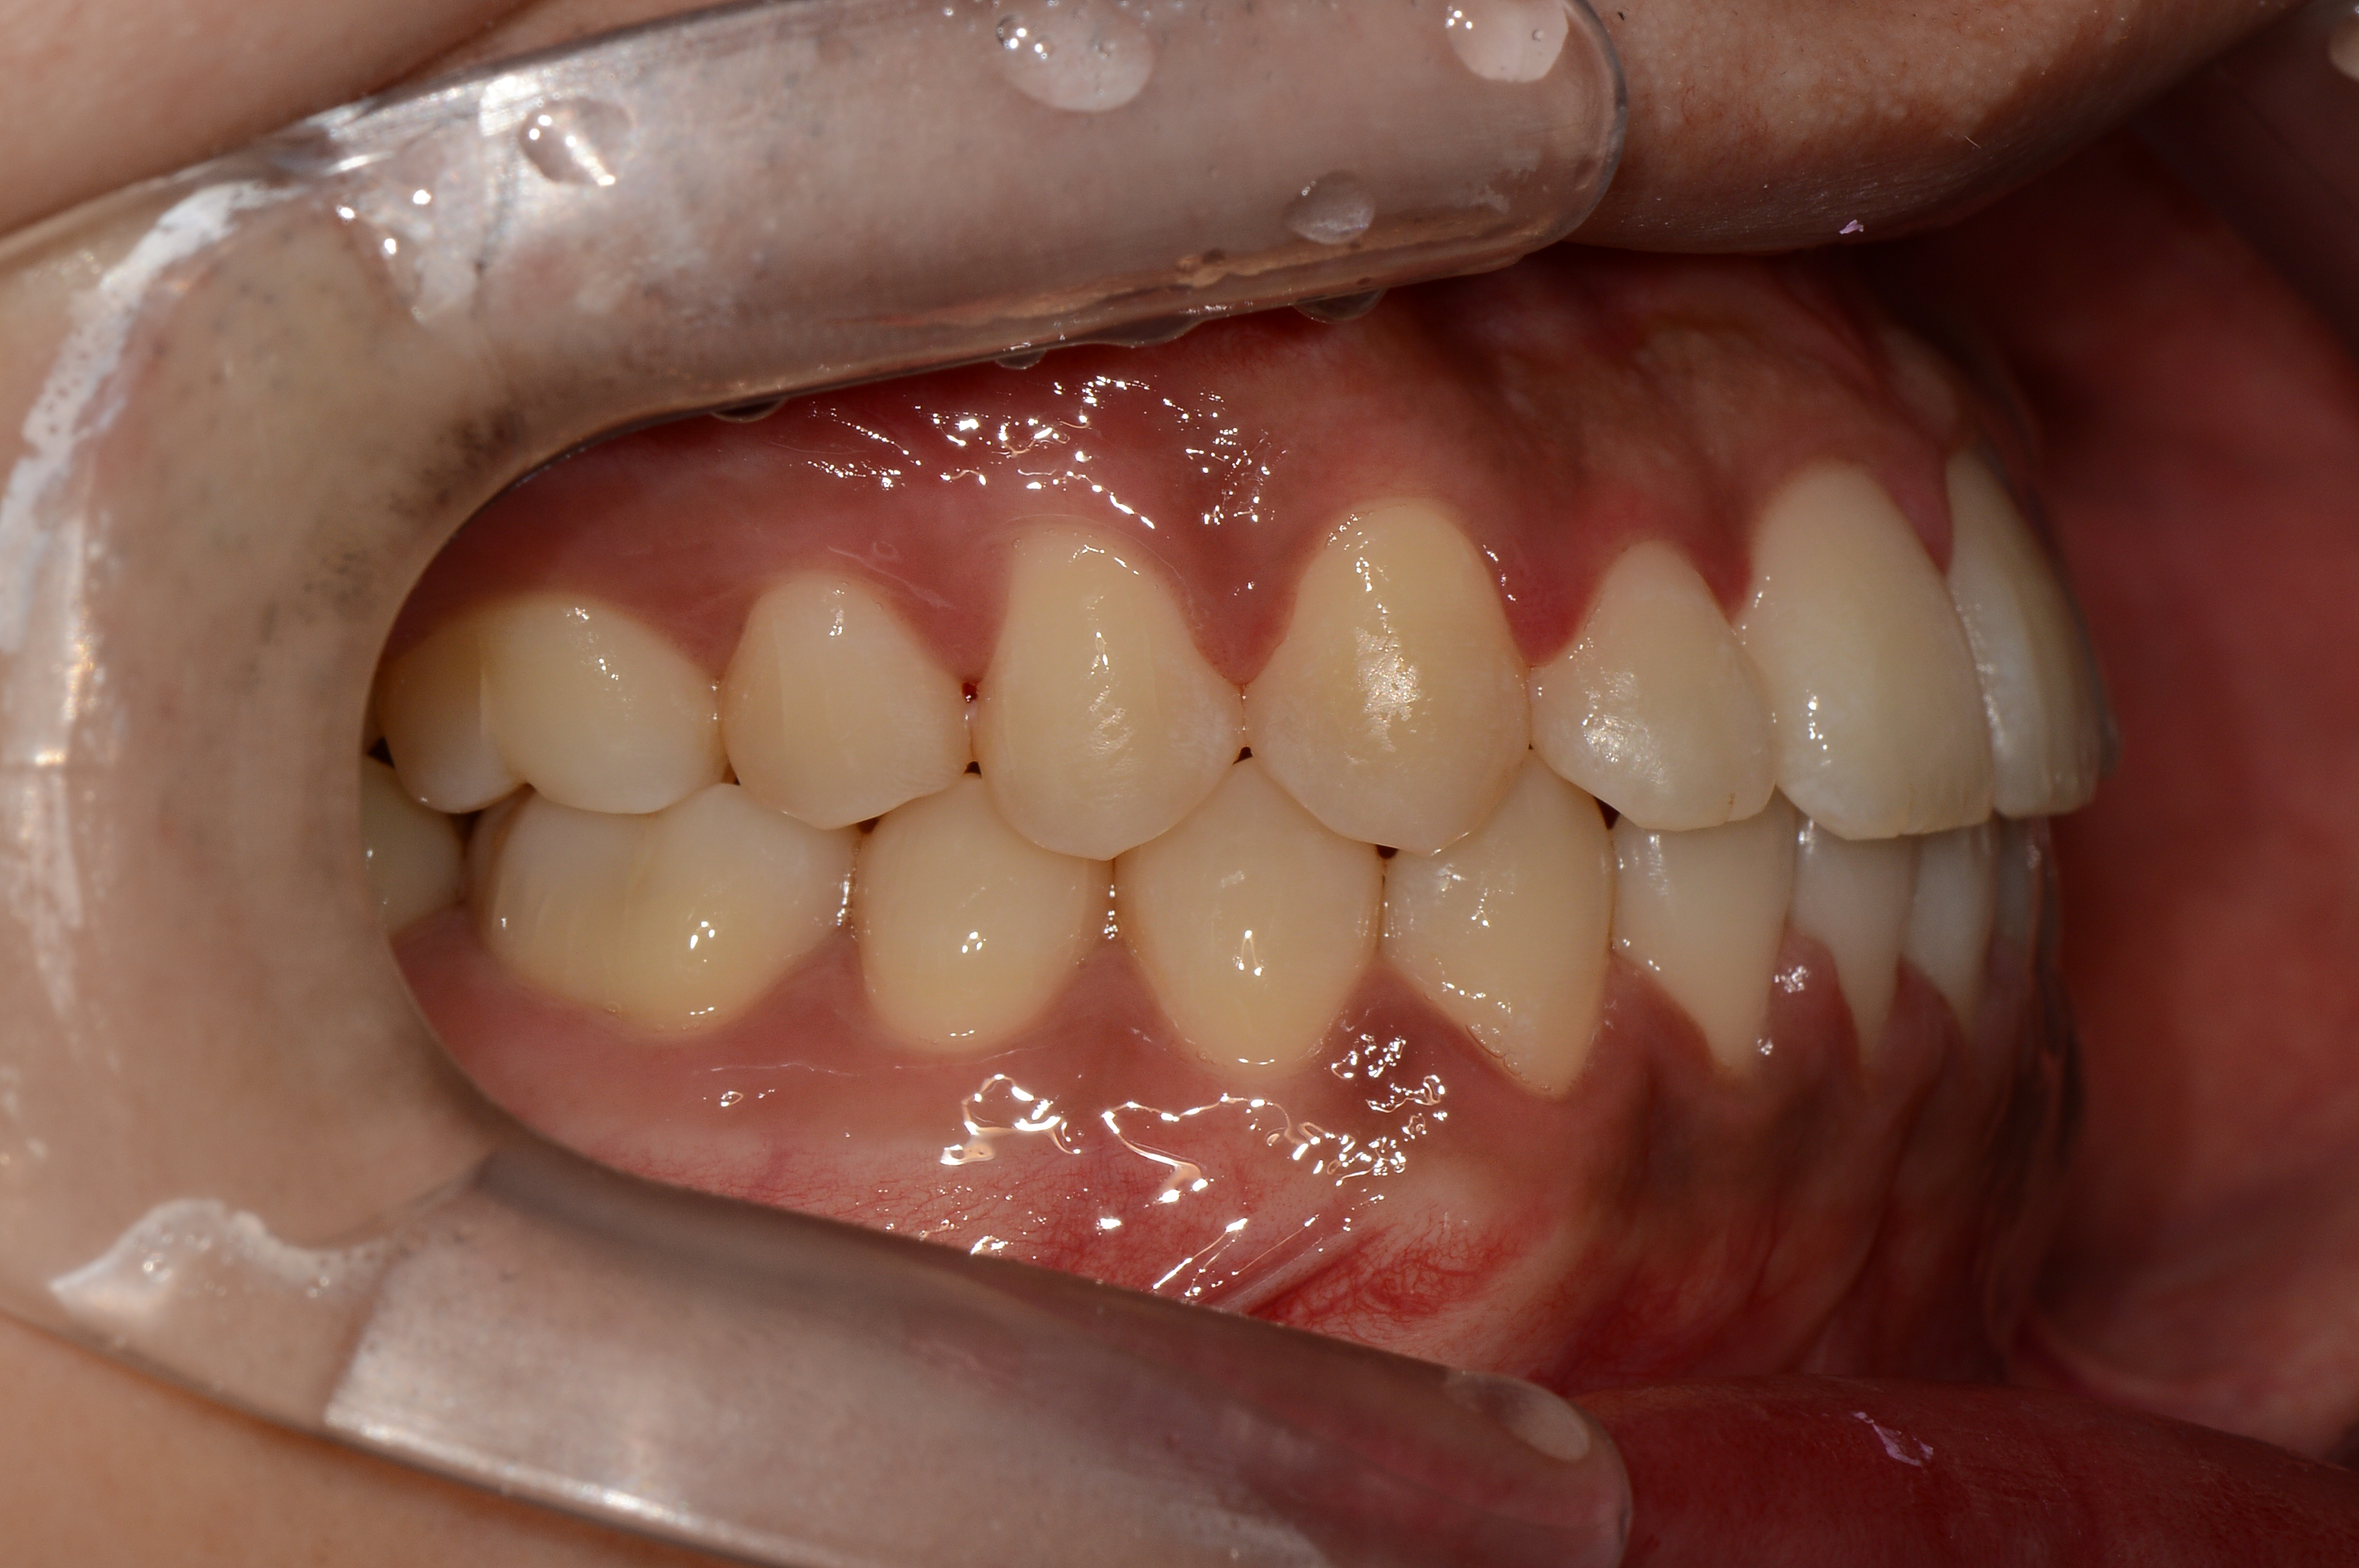

치료 전 사진입니다.